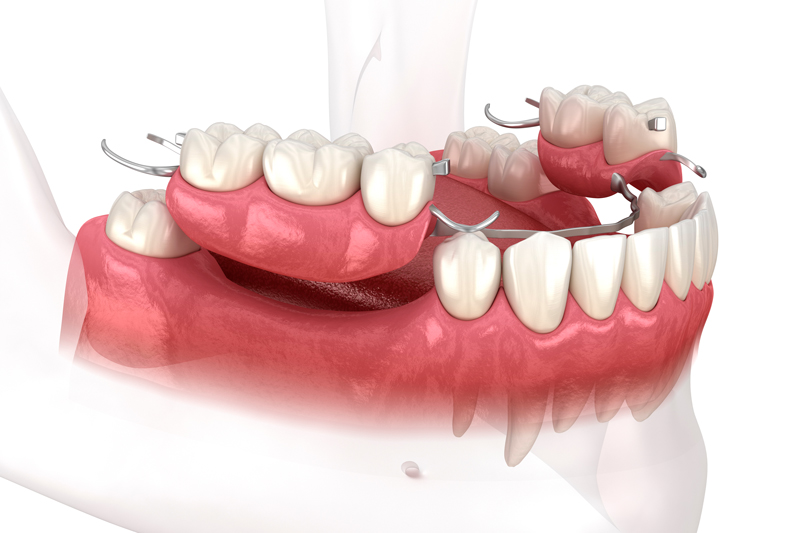

Implant supported dentures in Monroe, CT, also known as over-dentures, are a restorative tooth replacement option. Unlike traditional dentures that rest on the gums, implant

The implant supported dentures in Monroe, CT, also known as over-dentures, are a restorative tooth replacement option. Unlike traditional dentures that rest on the gums,

Unlike traditional dentures, which rest on the gums, implant supported dentures in Monroe, CT are anchored by dental implants. These tooth implants, typically made of